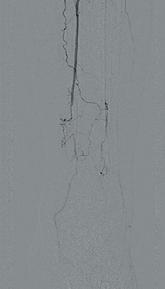

骨搬运手术前,微血管稀疏

搬运前血管稀疏